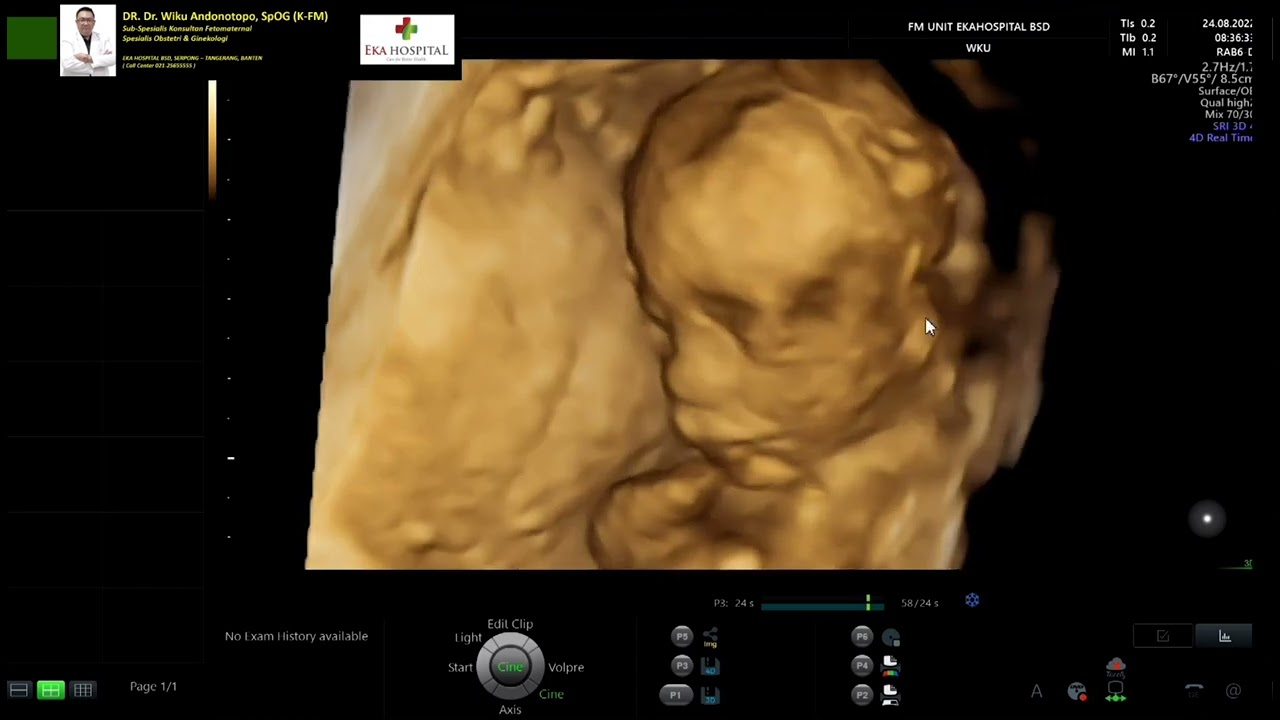

Trisomi 21 - Hygroma Colli (Dr Wiku Andonotopo)